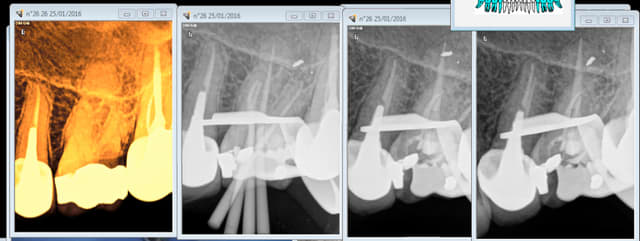

47 a symptomatique. Sur traitement ? -)

Capture d e cran 2016 01 26 17.54 - Eugenol